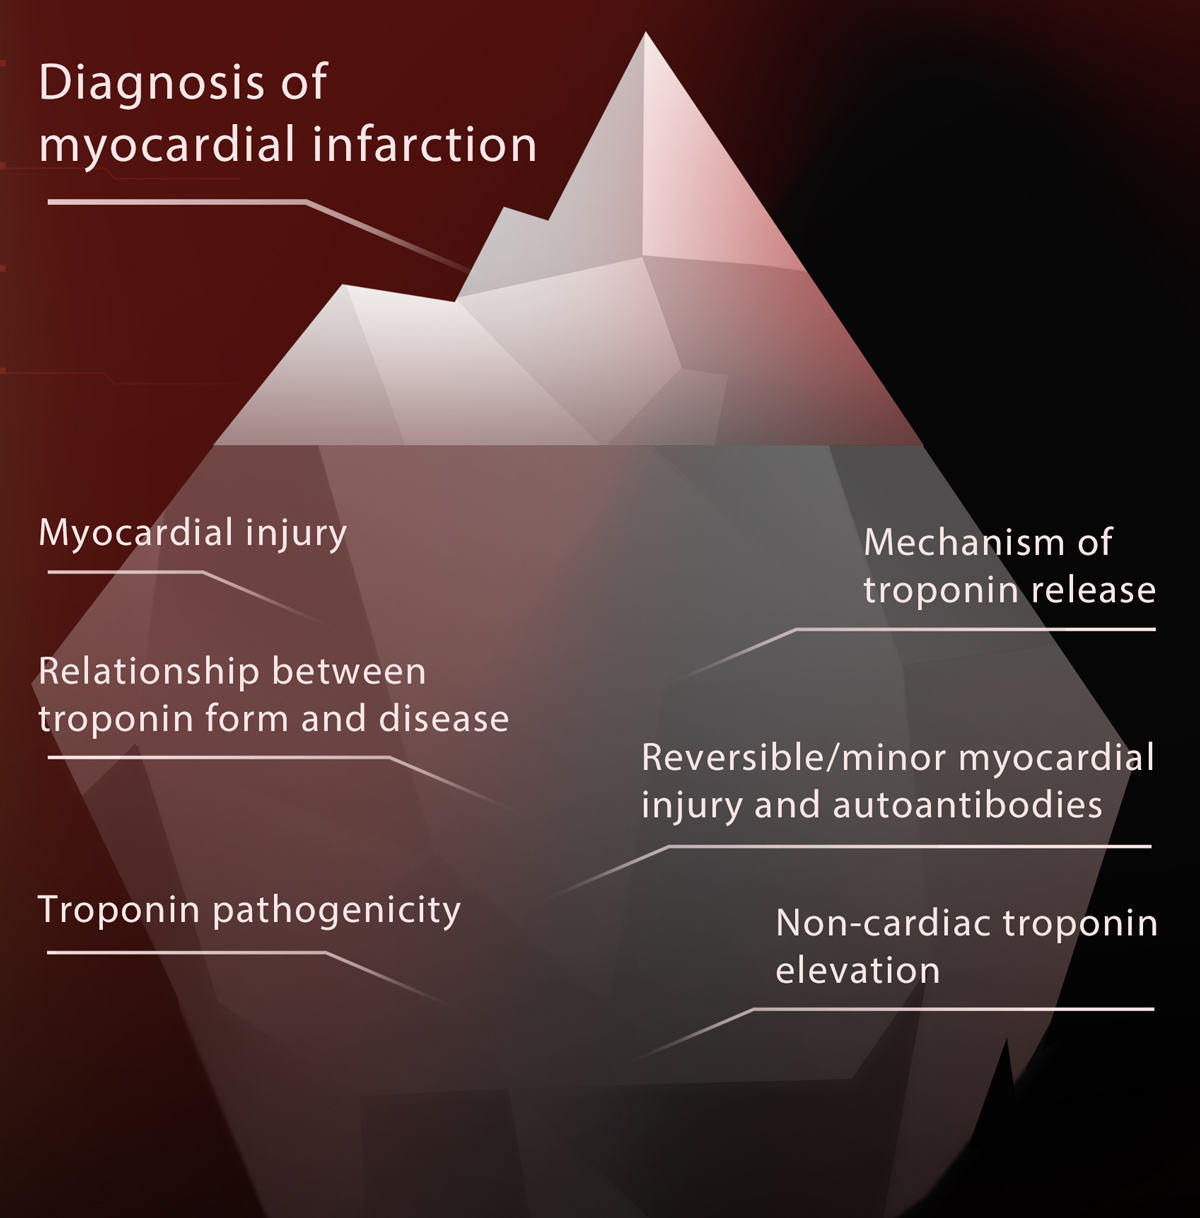

Tip of the iceberg

With the ongoing advances in troponin research, scientists have found that the diagnosis of myocardial infarction is only the tip of the iceberg in terms of the application of troponin. There is still much to explore: diagnosis of myocardial injury, mechanism of troponin release, and relationship between troponin composition and disease, and many more.

As the exploration is still underway, the view under the iceberg will provide immunoassay professionals with the motivation to forge ahead and innovate better reagents.